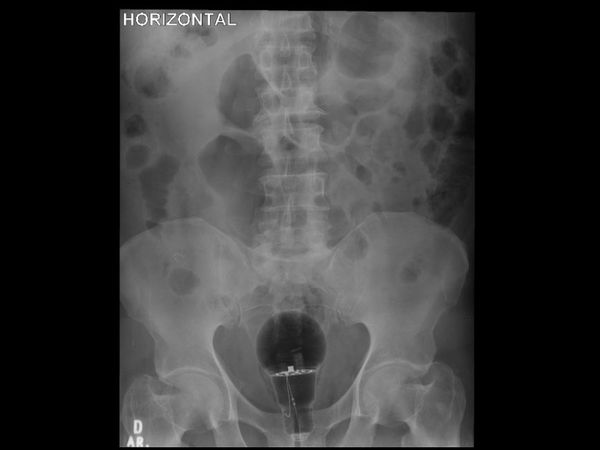

哥伦比亚的肠胃病学家兼内科医师Julian Pylori经常在推特上分享病例,上月他贴出一张X光照并解释这名53岁男性患者因肛门疼痛就医,经检查才发现他直肠里塞着一颗大灯泡,幸运的是这颗电灯泡并没有在体内破裂。

根据「每日邮报」报导,Julian Pylori于3月中在推特上写道,「53岁男性患者,直肠指诊难以触及的体内(未知)异物,该用内视镜移除?」发文附图的X光照可以看到,病患骨盆位置附近出现一颗大灯泡,甚至可以看到疑似金属电线的构造。医师表示,病患算是很幸运,因为灯泡没有破裂。